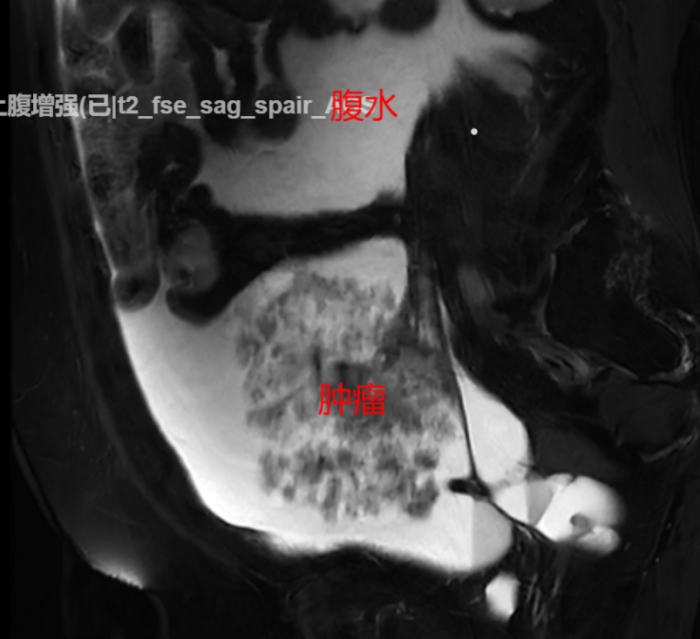

经过住院检查,医师发现何女士血清白蛋白值偏低,Ca125及HE4等卵巢癌指标异常升高。核磁共振结果进一步显示患者盆腔内有不规则团片影,其为肿瘤性病变或种植性病变的可能性较大,且患者腹腔、盆腔有大量积液,腹腔内脂肪间隙模糊,不排除外转移性病变的可能。

手术中,医疗团队成功抽出高达3000毫升的腹水,并完整切除了卵巢、输卵管、子宫以及所有盆底腹膜的多处转移病灶(包括多处膀胱及肠道浆膜层的种植病灶,较大直径为3cm),甚至精准切除了肾静脉水平的转移淋巴结,实现了对肿瘤细胞的全面“围剿”。术后,何女士在医护人员和家人的精心照料下,恢复情况良好,并顺利完成了后续化疗。